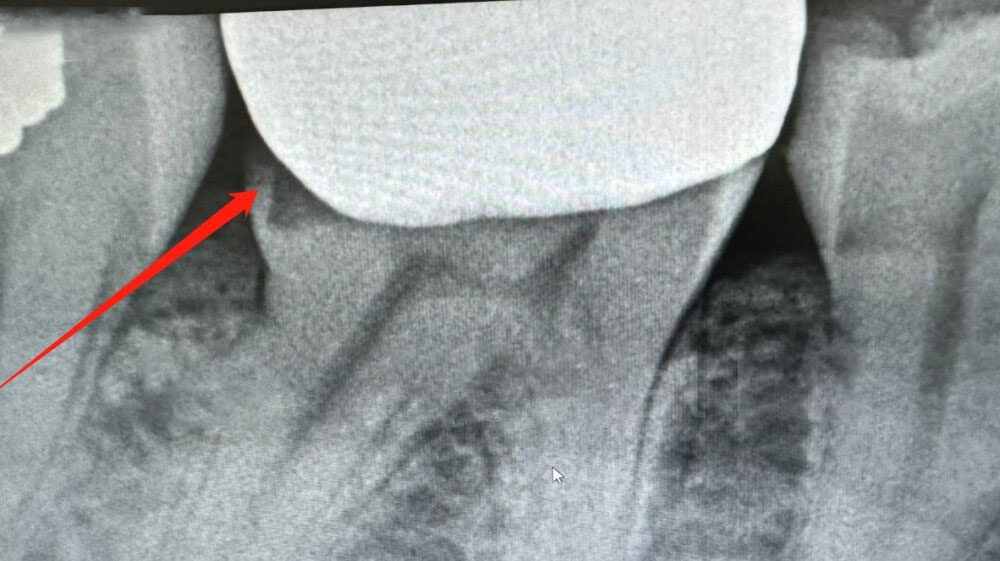

1. Checking X-ray

We immediately began investigation. We could see that the distal margin of the crown was open on X-ray. So we located the first-time scans and compare them with new scans. Let’s check what we found out.

Xray of the dental crown